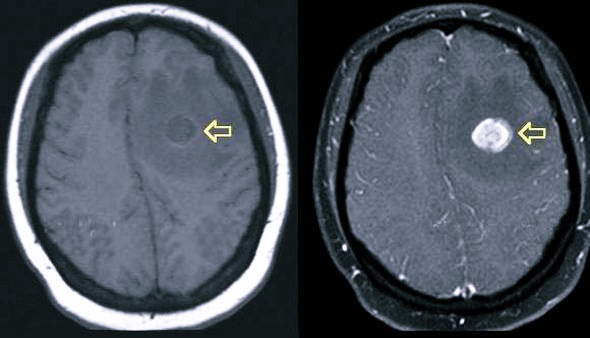

Обследование позволяет выявить опухоли, аневризм, проблемы с сосудами головы и нервной системой в общем, с его помощью отслеживается активность коры. Различают два режима МРТ: без контраста и с использованием веществ, повышающих контраст нужных тканей. В этом случае обычно вводятся соли гадолиния. Преимущество – высокая точность, за которую можно поплатиться возникновением аллергической реакции на вещество. Её появление специалист должен выявить заранее.

- опухоли ЦНС;